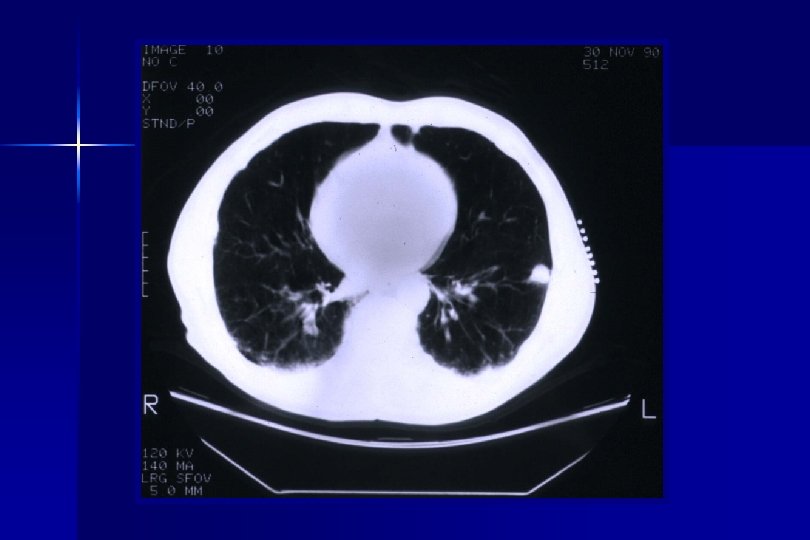

Eligibility Criteria Part I: Pre-Operative Criteria (Pre-Registration/Randomization): ● Patients must have a suspicious lung nodule for clinical Stage I NSCLC. ● Patient must have a mass ≤ 3 cm maximum diameter by CT size estimate: Clinical stage Ia or selected Ib (i. e. , with visceral pleural involvement. ● Patient must have a CT scan of the chest with upper abdomen within 60 days prior to date of pre-registration.